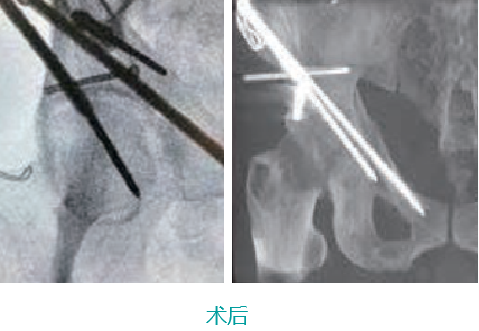

天玑II创伤手术—骨盆手术

天玑II 辅助骨盆髋臼骨折内牢靠术

基本情形:患者男,,,,,,,,69岁,,,,,,,,骨盆左侧髋臼前后柱损伤

机械人辅助优势:天玑II机械臂最后控制快速选择和执行手术妄想,,,,,,,,通道螺钉精准定位,,,,,,,,镌汰术中透视。。。。。。。

病例泉源:北京积水潭医院